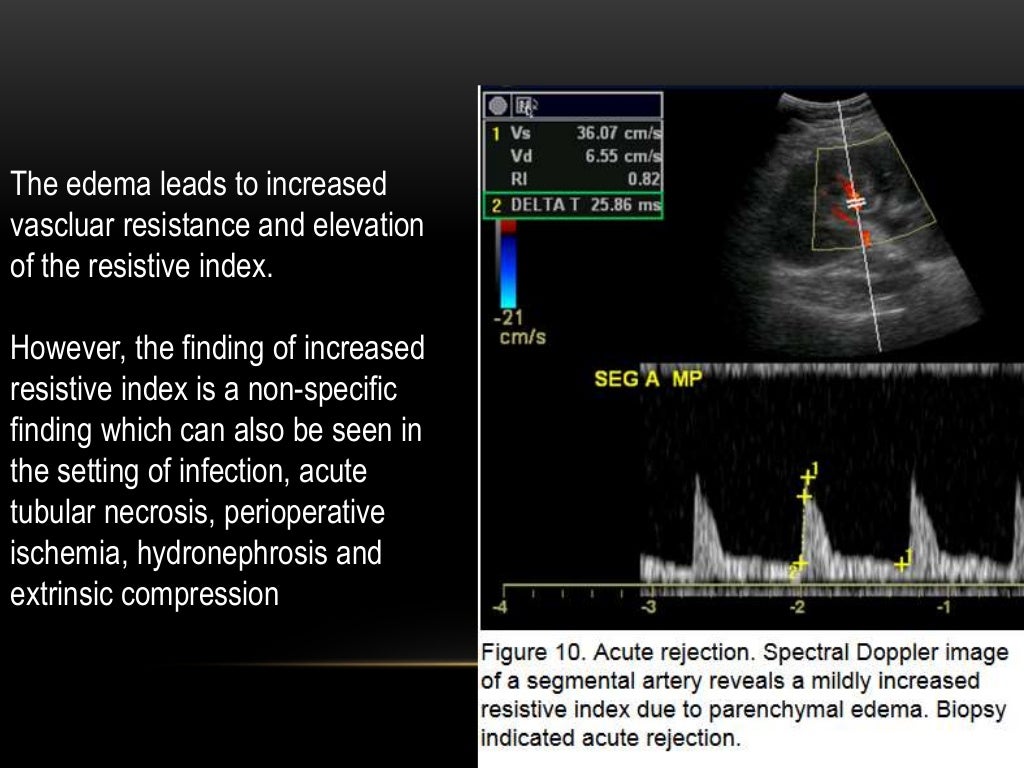

WebLa insuficiencia renal es un proceso que expresa la pérdida de capacidad funcional de las nefronas, con tendencia a empeorar y ser irreversible. En este artículo se revisan. WebCómo se realiza. La persona se estira y se le aplica un gel conductor a base de agua en el área del cuerpo que se quiere estudiar para facilitar la transmisión de las ondas. WebEl Eco Doppler Renal, se utiliza en la evaluación cardiovascular en caso de sospechar que la hipertensión arterial detectada en el exámen clínico, pueda corresponder a. WebTomar FACTOR AG O MYLANTA GAS con cada comida. Día previo al examen: cenar liviano, teniendo en cuenta no ingerir los alimentos antes mencionados, ni bebidas con. WebTecnica de como estudiar la arteria renal en vivo, directamente sobre el paciente. https://institutodomina.orgIG: @dr.ricardodomina#Doppler renal #Hipertensi... WebLa ecografía Doppler es una prueba no invasiva que calcula el flujo de la sangre en los vasos sanguíneos haciendo rebotar ondas sonoras de alta frecuencia. WebSi te van a realizar una ecografía-doppler estas son las cuestiones que debes tener en cuenta: Duración : la ecografía-doppler dura unos 15 minutos. Ingreso : se suele realizar.

WebLa ecografía Doppler funciona midiendo ondas sonoras que se reflejan en objetos en movimiento, como los glóbulos rojos. Esto se conoce como efecto Doppler. Hay. WebUtilidad del ultrasonido Doppler renal para el diagnóstico de estenosis de las arterias renales con la propuesta de un nuevo índice renal-renal, y análisis del índice de. WebSe debe comenzar examinando la aorta con el paciente en decubito dorsal, desde epigastrio en el plano longitudinal localizando el tronco celiaco y luego la.

WebLa ecografía Doppler es una prueba no invasiva que calcula el flujo de la sangre en los vasos sanguíneos haciendo rebotar ondas sonoras de alta frecuencia. WebSi te van a realizar una ecografía-doppler estas son las cuestiones que debes tener en cuenta: Duración : la ecografía-doppler dura unos 15 minutos. Ingreso : se suele realizar. WebDE LA ARTERIA RENAL MEDIANTE DOPPLER La estenosis de la arteria renal mediante la técnica Doppler se detecta de dos formas: 1) por la alteración de la forma de onda en.